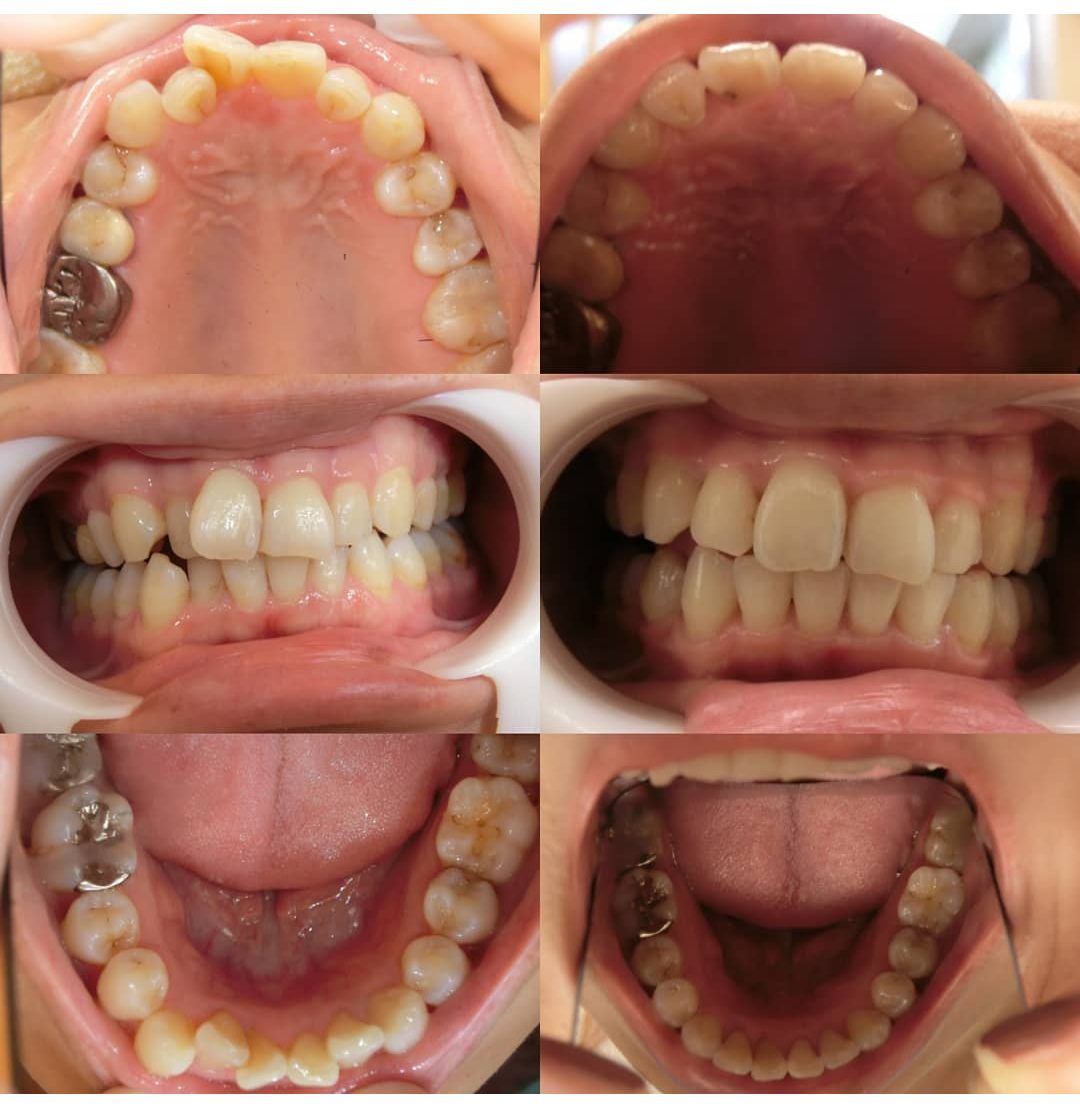

主訴

上顎前歯の傾きと、叢生(歯の重なり)が気になる

治療期間

1年半ほど